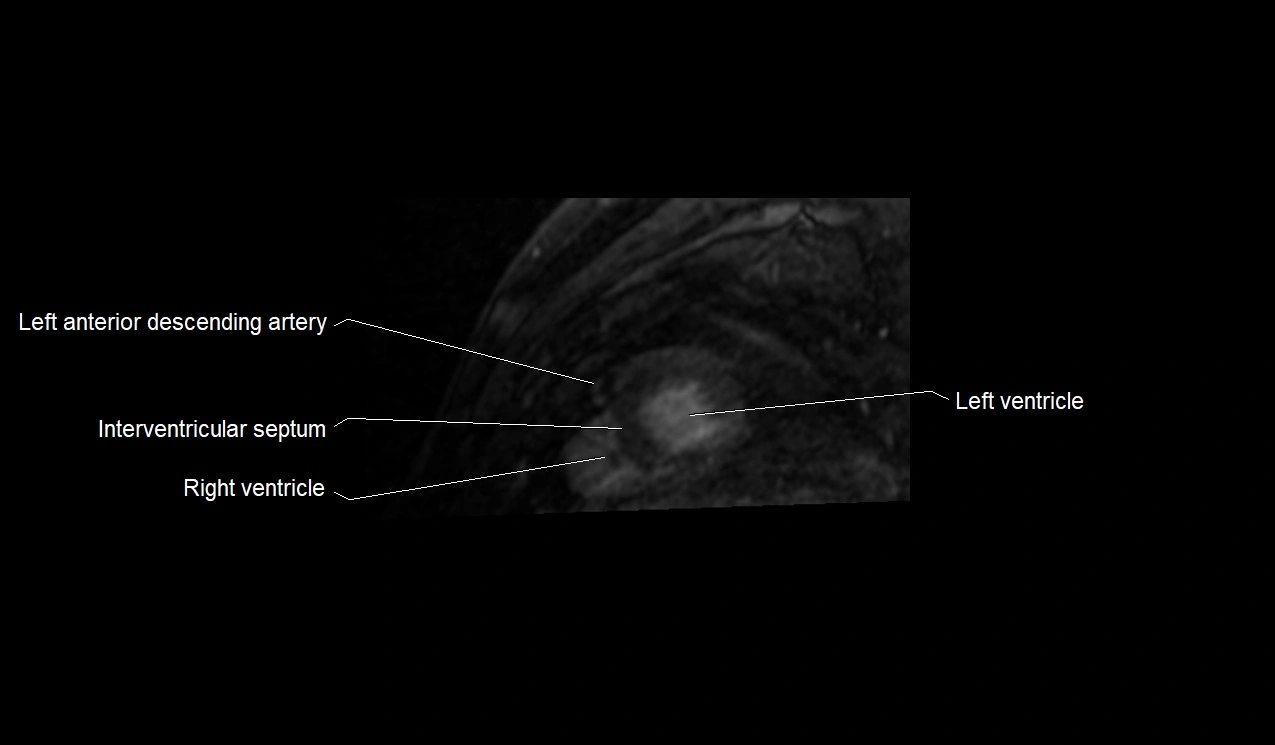

MRI image